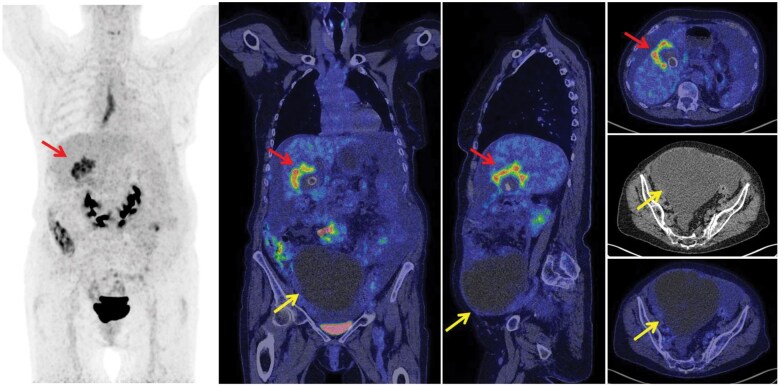

Abstract Image